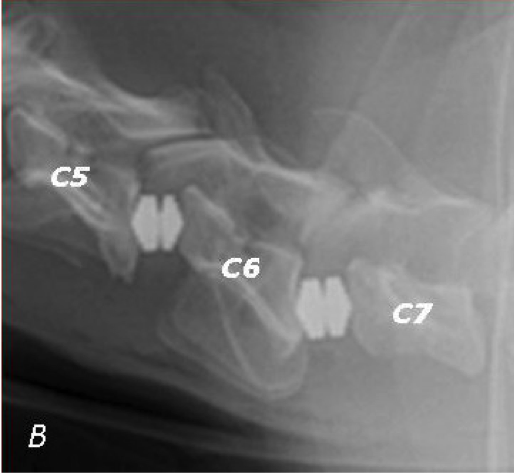

Cette carte de concepts créée avec IHMC CmapTools traite de: Alex-Syndrome-de-Wobbler, la sécrétion de calcitonine qui ralenti la résorption osseuse du canal vertébral, Les chiens de 6 mois à 6 ans car les origines du syndrome sont diverses. Tels que Berger allemand, Nourriture riche en énergie entraine une croissance trop rapide, devient trop étroit . pincement de la moëlle osseuse, de luxations ce qui pince ou écrase la moëlle épinière et/ou les nerfs, un facteur génétique et/ou alimentation trop riche en énergie, la sécrétion de calcitonine par la glande thyroïde, Une malformation et le déplacement des vertèbres cervicales si le chien possède un ou plusieurs critères agravant (long cou, grande tête, croissance rapide) dû à un facteur génétique et/ou alimentation trop riche, à la moëlle épnière qui continue sa croissance indépendamment . pincement de la moëlle osseuse, Syndrome de Wobbler entraine Des douleurs cervicales (inconstantes), une ataxie bilatérale, une parésie, une myélopathie, une radiculopathie, une amyotrophie, Syndrome de Wobbler est diagnostiqué Par différents examens médicaux : - un examen neurologique - un examen radiographique des vertèbres cervicales pour dépister : une sténose du canal vertébral, une malformation d'une vertèbre (C7) - une myélographie pour déterminer la localisation, la sévérité et la nature de la compression - un scanner pour déterminer la localisation, la sévérité et la nature de la compression - un IRM pour une bonne visualisation des tissus mous, Les chiens de 6 mois à 6 ans car les origines du syndrome sont diverses. Tels que Doberman, Régime riche en calcium provoque une hypercalcémie, une hypercalcémie qui entraine la sécrétion de calcitonine, devient trop étroit par rapport à la moëlle épnière qui continue sa croissance indépendamment, une malformation ou une formation asymétrique des vertèbres ce qui pince ou écrase la moëlle épinière et/ou les nerfs, Syndrome de Wobbler est traité Soit par : - un traitement conservateur, pour éviter l'apparition des symptomes chez les animaux à risque - un traitement médical, pour stabiliser - un traitement chirurgical à visée curative basé sur : o arthrodèse des VC o corpectomie o laminectomie Soit plusieurs de ces traitements combinés., Syndrome de Wobbler consiste en Une malformation et le déplacement des vertèbres cervicales si le chien possède un ou plusieurs critères agravant (long cou, grande tête, croissance rapide), un facteur génétique et/ou alimentation trop riche en calcium, ralenti la résorption osseuse du canal vertébral qui devient trop étroit